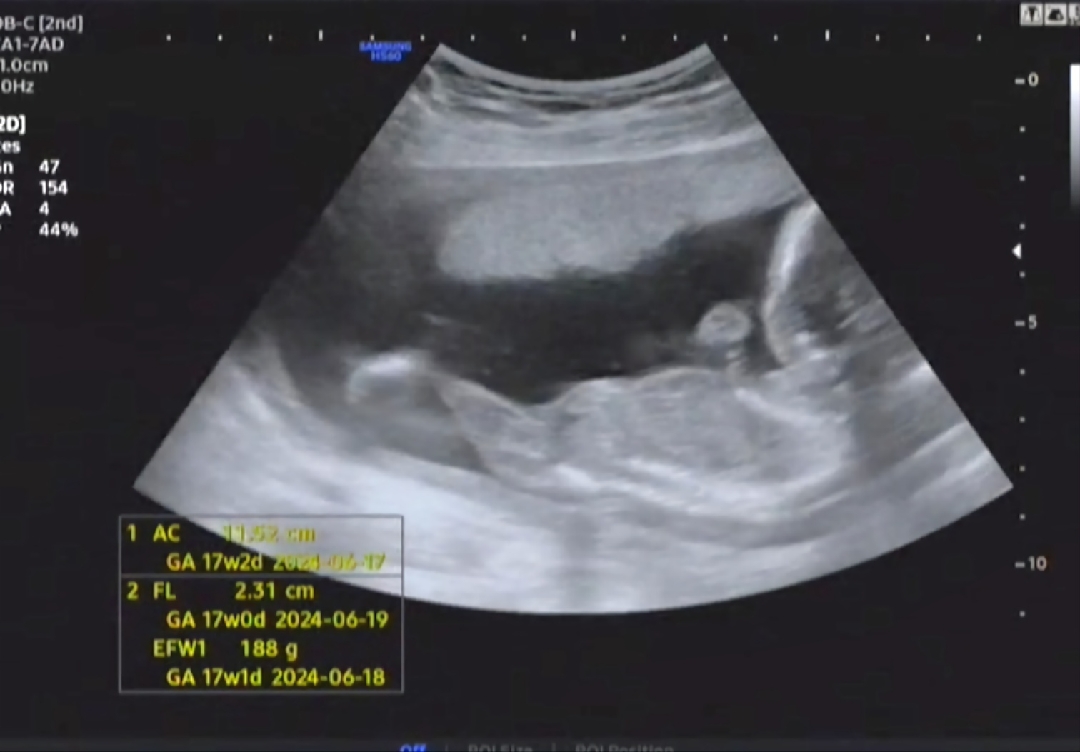

딸이라고 하시네요 첫째가 아들이라 둘째 딸이길 바랬는데 ~~~ㅎㅎ 태명은 반짝이에욤

18주차예요~~~~반기워욤🤗